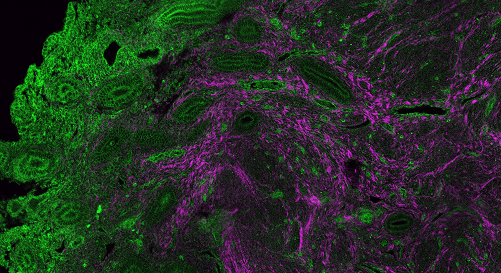

Legend : Endometrium–myometrium junction in a patient with adenomyosis: endometrial glands invading the collagen-rich myometrium. SHG microscopy – Cochin Institute.

This project aims to better understand the underlying mechanisms of endometriosis by studying the physiology of the uterine muscle, the myometrium. The disease is associated with myometrial hypercontractility, which is hypothetically linked to hormonal receptor overexpression, aberrant innervation, or muscular disorganization. To investigate this hypercontractility, we have combined functional and histological approaches. Ex vivo myometrial contractility is assessed using tissue slices from hysterectomy specimens subjected to oxytocin stimulation, a key regulator of uterine contractions. This method, which preserves the structural integrity of the tissue from the serosa to the endometrium, enables the analysis of peristaltic waves frequency, amplitude, nucleation sites, and propagation velocity. In parallel, immunohistochemical analyses of large myometrial sections are performed to map the distribution of oxytocin receptors along the serosa–endometrium axis. We find that contraction frequency in patients with endometriosis and/or adenomyosis is significantly higher than in controls. Organ-bath contractility involves the entire myometrial thickness from endometrium to serosa, in contrast with in vivo imaging observations (MRI/US) that usually highlight contractions close to the endometrium. We show that oxytocin can stimulate the nucleation of contractile waves close to the endometrium, correlating with high local oxytocin receptor expression at this site and supporting the hormonal regulation of wave directionality.